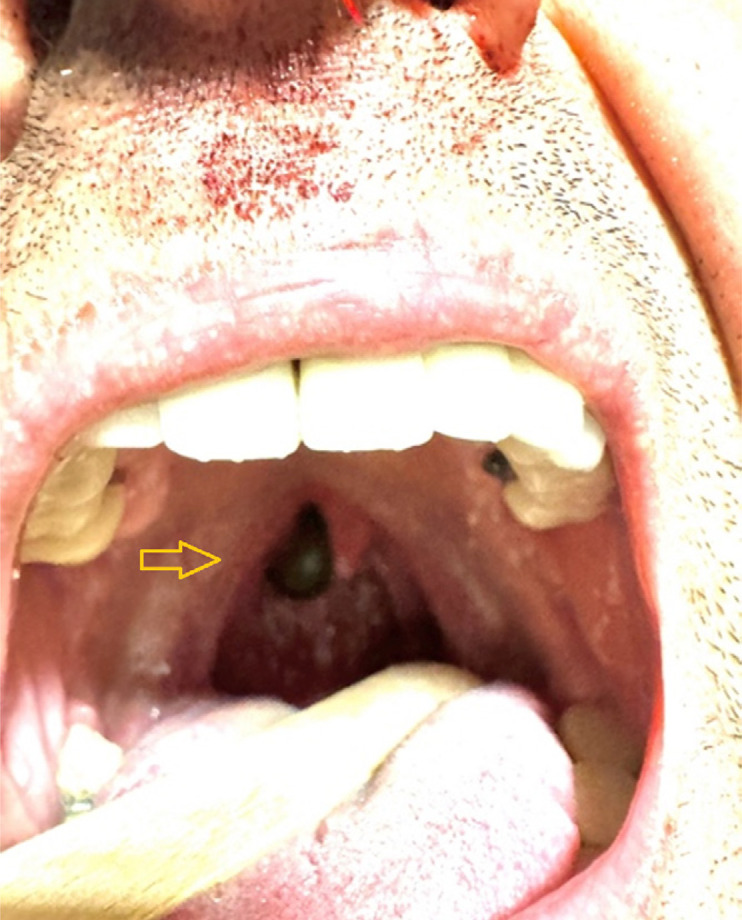

Leeches are segmental worms commonly found in fresh water in tropical regions. They can enter the human body via the consumption of contaminated water or through the mouth and nose during washing, generally affecting the upper airway and digestive tract. During the blood-sucking process, the leech releases the anticoagulant enzyme "hirudin" from the wound site into the host's circulation together with an anesthetic to prevent the host from feeling its attachment. Leech endoparasitism is a very rare cause of epistaxis. We report a case of a living leech lodged in the posterior nasal floor in a patient that presented to the emergency department with unilateral epistaxis and a difficult diagnosis.